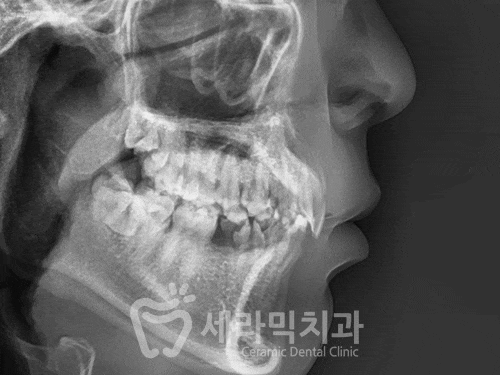

오늘 살펴볼 치아교정전후 사례는 과개교합, 거미스마일, 치아 벌어짐을 동시에 갖고 있던 분으로, 세라믹치과의 치아교정과 임플란트를 통해 불편하게 느끼시던 부분을 깔끔하게 해결하신 분의 이야기입니다. 과개교합이란 윗니가 아랫니를 과도하게 덮고 있는 것을 과개교합이라고 하며, 딥바이트(Deep bite)라고도 합니다. 과개교...

● 과개교합, 거미스마일, 치아 벌어짐 치아교정전후 사례자 프로필 ●

교정 시작 나이 : 23세

교정 시작 이유 : 치아 벌어짐, 과개교합

교정 예상 기간 : 18~20개월

치료방법 : 비발치 세라믹교정

● 치료 방법 ●

치아배열 개선을 위한 '비발치 교정'으로

위 쪽 치열을 개선합니다.

아래에는 좌우 2개의 치아(#35, #45)가 없는 상태여서,

치아교정으로 치아배열을 맞추더라도 잇몸 공간이 남기 때문에

벌어진 공간을 정리하고 임플란트를 식립하기로 합니다.